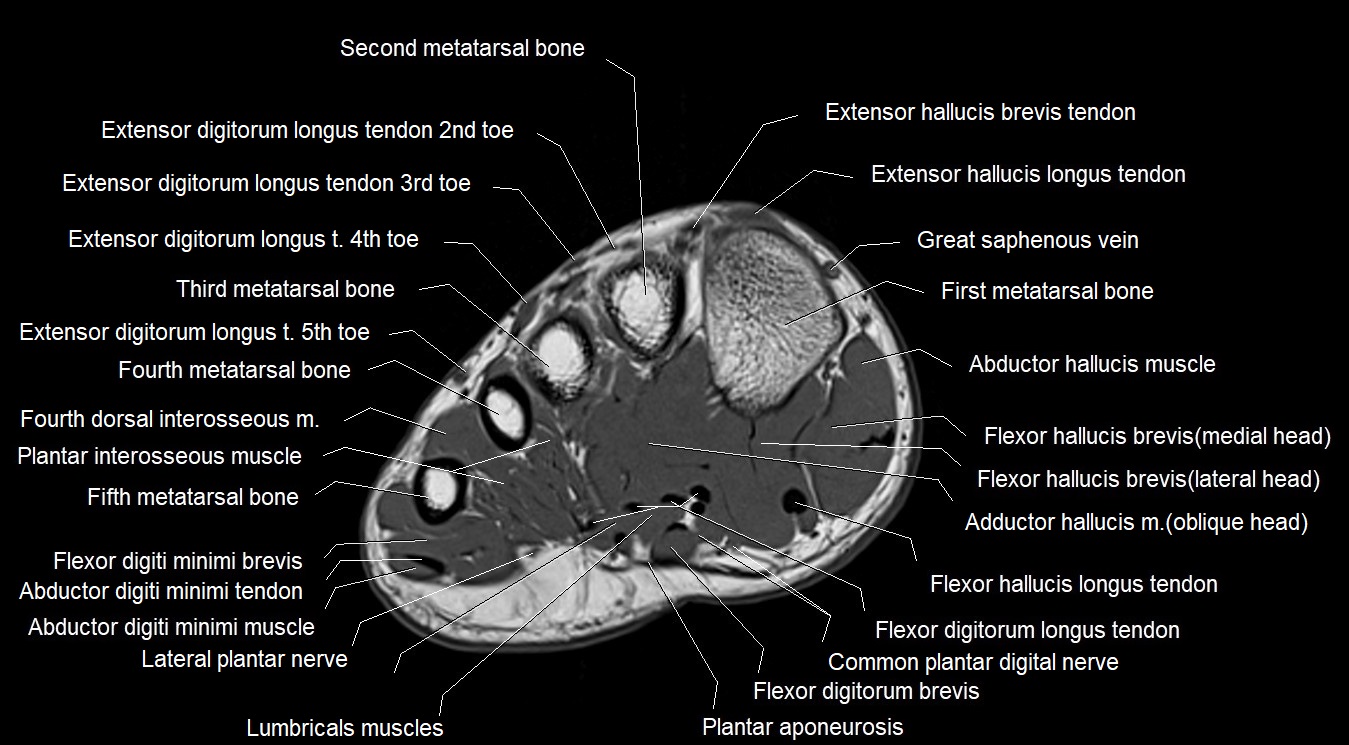

MRI image